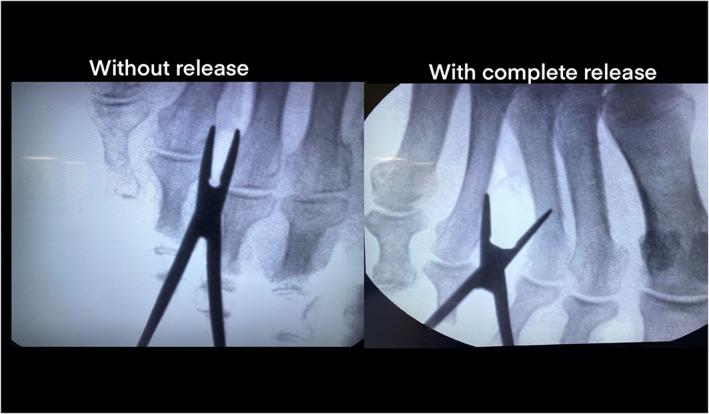

MATERIALS, METHODS, AND RESULTS: The DTML was visualized in 10 fresh frozen donated body to science-feet (eight male and two females, five left and five right) using an US device (GE Logic R7; 13 MHz linear probe, Madrid, Spain). Consecutively, minimally invasive ultrasound-guided surgery was performed. Exclusion criteria of the donated bodies to science were previous history of forefoot surgery and space occupying mass lesions. The complete release of the ligament was achieved in all specimens without damage of any important anatomical structures as proven by anatomical dissection.

The results of this study indicate that our novel approach of an ultrasound-guided release of the DTML is safer and more effective compared to blind techniques. The DTML could reliably be visualized and securely cut through a dorsal, minimally invasive surgical incision of only 2 mm.